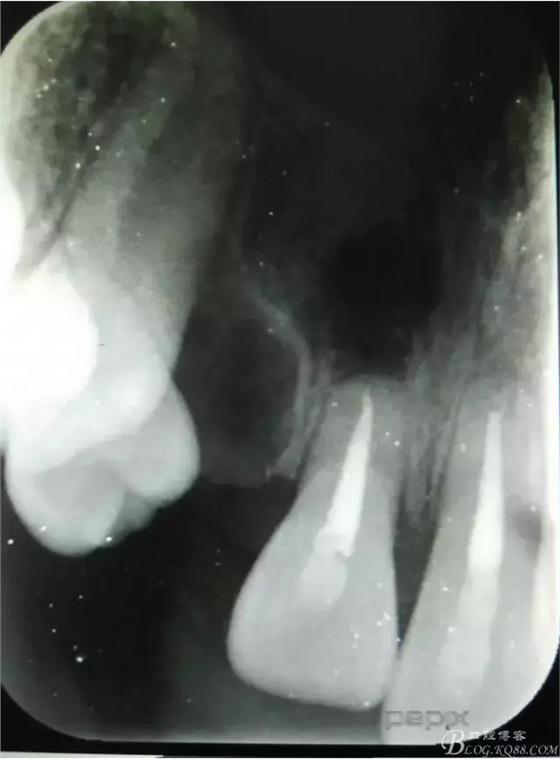

患者、李xx、男、15歲,主訴:牙不齊,矯正牙齒。??茩z查:發(fā)現(xiàn)11、21根尖三分之一折斷,患者否認有外傷史。正畸科治療建議如圖1.。術前簽手術同意書。